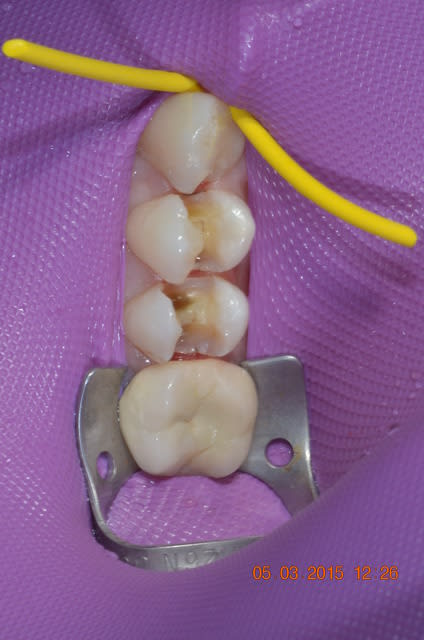

06/03/2015 à 11h05

le split dam c'est vraiment 10 secondes a mettre et un confort de travail vraiment top l'étancheite est relative mais pour trois soins c'est déjà très efficace.

photos d'hier